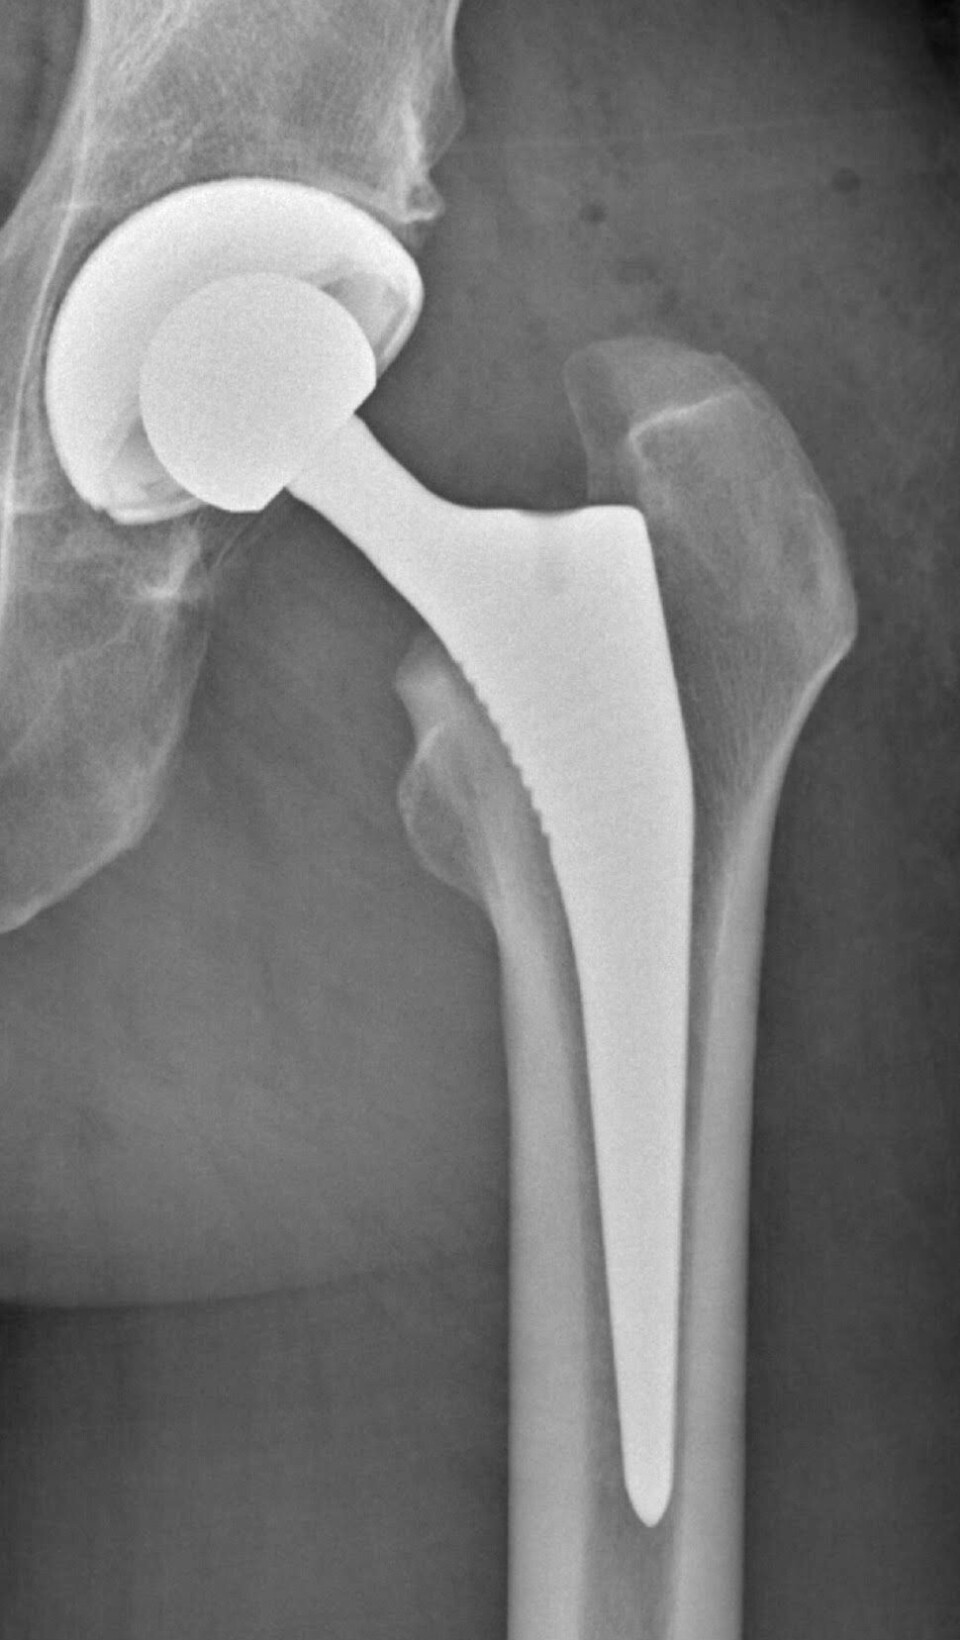

Hofteprotese

Etter seks år med en del løping og mange vondter samt en ny skavank som stadig ble mye verre, bestemte jeg meg for mitt andre titantilskudd, en protese i venstre hofte (usementert total protese Polar3) med operasjon i februar 2022. Trolig ble belastningen for stor for hoften både før og etter kneoperasjonen.

Min første protese som 50-åring kom i relativt ung alder, men sett i ettertid burde kneoperasjonen vært utført mye tidligere! Livskvaliteten var lenge betydelig redusert for meg som er glad i fysisk aktivitet. Slitasje ved å gå rundt og humpe kan i tillegg ødelegge andre ledd, i mitt tilfelle hoften på motsatt side.

Dette har nok også en sammenheng med at en protese har begrenset levetid og muligens slites raskere av en aktiv person. Dersom innfestningspunktet (benet) blir ødelagt, kan det være komplisert å få festet en ny protese.

For meg er aktivitet så viktig at jeg eventuelt heller får ta en ny operasjon dersom det blir nødvendig. Det er bedre med litt fysisk lidelse enn å være psykisk nedbrutt og deprimert resten av livet. Forhåpentligvis utvikles det også nye og bedre operasjonsmetoder etter som årene går!